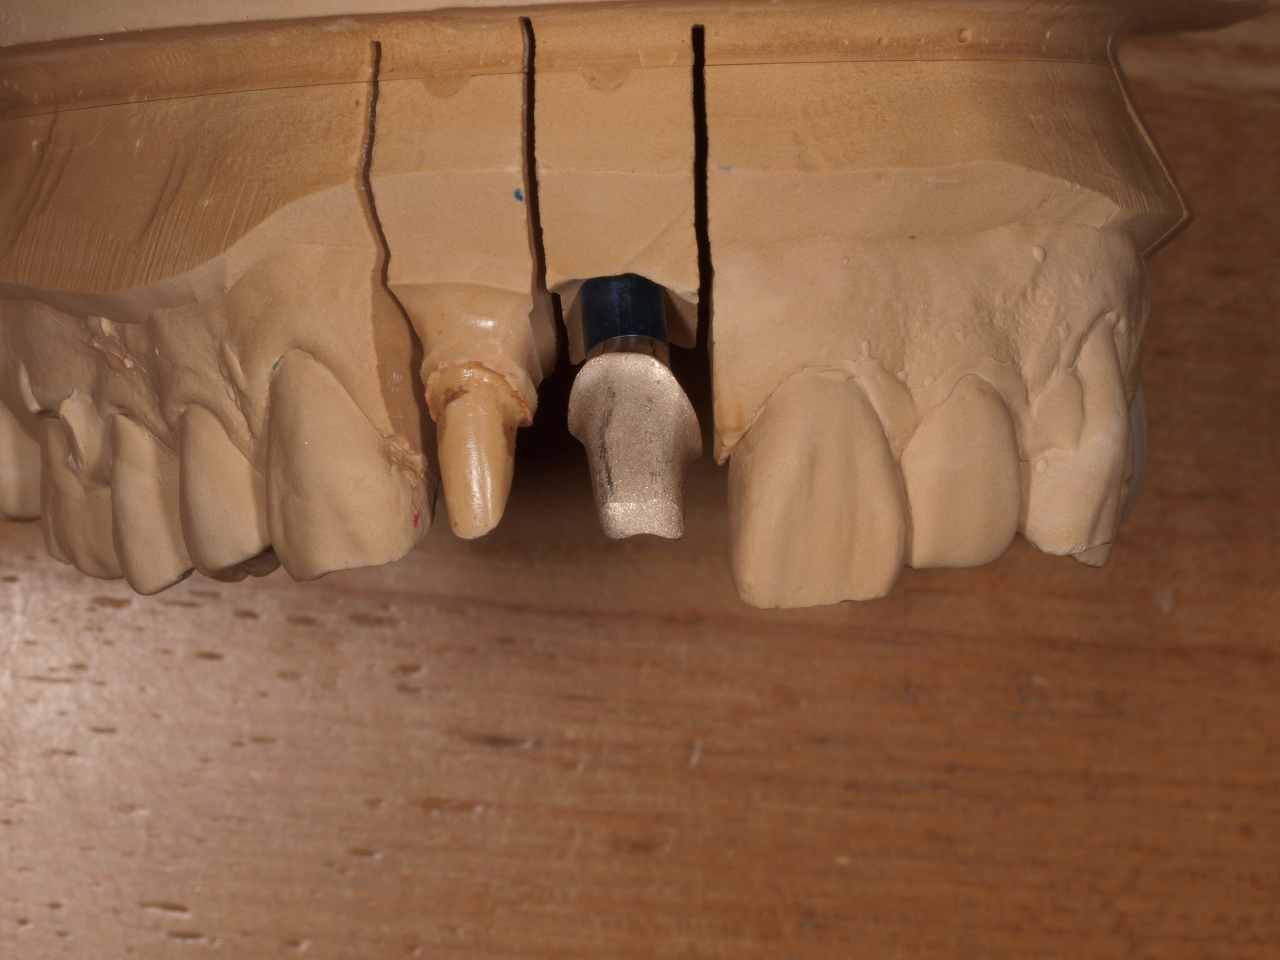

前歯部のアバットメントはゴールドにて仕上げています

このようなエマージェンスプロファイルを取っています

インプラントからジルコニアクラウンへの立ち上がりが大切になります

清掃性の問題が埋入時に決まります

ジルコニアクラウンの色味をしっかりと出すためアバットメントは大き過ぎずの形態を技工所とも日々打ち合わせしています